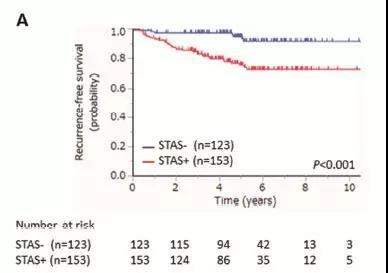

图表A:无STAS(89.5%)和STAS阳性(71.7%)病人5年无复发生存率有显著差异,

STAS引起术后肿瘤复发率增加,肿瘤复发包括局部复发和远处转移